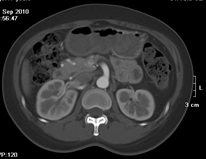

目前臨床對于16層CT的認可主要集中在三維成像領域上的突破.在16層CT的產品平臺上,常規(guī)掃描就能實現(xiàn)滿足三維成像的要求,因此16層也被稱為三維CT,三維成像給臨床診斷帶來了更精確更豐富的診斷信息,我們以臨床為例:

如上圖所示,相鄰的三張軸位圖像未見明顯異常,根據(jù)傳統(tǒng)軸位圖像很難得到準確的臨床診斷。

同一病人利用容積數(shù)據(jù)進行三維處理后,高品質MPR和三維圖像上則清晰顯示了縱向排列的腹腔干與腸系膜上動脈相鄰近,血管發(fā)生變 異,近端血管閉塞,為臨床提供了精確的診斷信息。

從上面的例子可以看到,能否為臨床提供高品質的三維影像成為了16層CT的核心價值,而東芝新一代的 全景三維16層CT擁有最為  先進的3項核心技術,在16層核心價值上的表現(xiàn)自然值得期待。